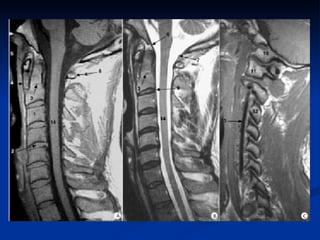

IRM Multi planaire Multi paramétrique Remarquable résolution en contraste Anodine

IRM cervicale Technique « Scowt view » Séquence sagittale TSE T2 Séquence sagittale TSE T1 Coupe axiale EG T2 Séquence EG à effet myélographique Injection de PC non systématique

IRM dorsale  coupes  : une acquisition de repérage est réalisée dans un plan frontal  plans de coupe:  plan sagittal objectivant l'ensemble du rachis plan axial transverse pour une étude segmentaire épaisseur de coupe ne doit pas dépasser 3 à 4 mm dans le plan sagittal et 5 à 10 mm dans le plan axial

IRM dorsale Un examen IRM du rachis thoracique comprend le plus souvent : une séquence pondérée en T1, avec des coupes fines (3 à 4 mm) dans un plan sagittal  une séquence pondérée en T2 dans le plan sagittal ;  si besoin, des coupes axiales pondérées T1 ou T2 suivant l'indication.

IRM cervicale Technique« Scowt view » Séquence sagittale TSE T2 Séquence sagittale TSE T1 Coupe axiale EG T2 Séquence EG à effet myélographique Injection de PC non systématique

IRM dorsale Unexamen IRM du rachis thoracique comprend le plus souvent : une séquence pondérée en T1, avec des coupes fines (3 à 4 mm) dans un plan sagittal une séquence pondérée en T2 dans le plan sagittal ; si besoin, des coupes axiales pondérées T1 ou T2 suivant l'indication.